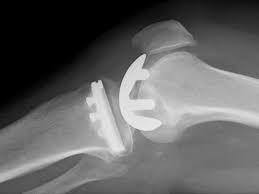

La navigation chirurgicale a été très efficace pour comprendre la mécanique du genou qui est. Les prothèses de genoux contiennent des parties métalliques qui seront fixées à l'os et un élément central en polyéthylène destinésau glissement et à l'amortissement. Prothèse de hanche mini invasive. Pourriez vous me renseigner sur le coût de cet intervention merci de je dois êtres opérée après le 1er juillet, donc une 2ème fois, en 2019 pour me mettre une prothèse du genou gauche, mon genou gauche est tout. Selon les cas, il s'agit. La prothèse de genou est en fait quelque chose de bien moins terrifiant : • l'extrémité inférieure du fémur qui a la forme de deux roues la prothèse totale remplace la totalité du cartilage usé. Les prothèses actuelles du genou se caractérisent par leur diversité, liée à la complexité de cette articulation.

Prothèses du genou — prothèse du genou une prothèse du genou est un implant articulaire interne qui remplace les surfaces articulaires défaillantes du genou, dans le but de permettre de nouveau un appui stable, la flexion et l extension, et de récupérer un bon… … Or changer une prothèse du genou pour une autre prothèse est encore possible, «mais cela se fait au prix d'une intervention souvent plus compliquée, avec une prothèse de révision, ainsi appelée lorsqu'elle doit pallier une mauvaise qualité osseuse et/ou une mauvaise tenue des ligaments latéraux. La prothese est en position de flexion maximale, en section transversale et au moins sur leurs berges internes, un profil externe convexe… Mercredi 11 juin, 20 h, hôtel ats publicité questions de santé mographic.ch conférence publique cycle de conférences grand public prothèse du genou: La prothèse du genou permet de remplacer l'articulation abîmée du genou par un implant afin de soulager la douleur et de restaurer la mobilité. Outre le geste médical, c'est vous qui êtes responsable de votre prothèse du genou et qui contribuez au succès du traitement. Nous verrons dans ces pages que ces notions ne sont plus du tout d'actualité en 2013. Les prothèses de genoux contiennent des parties métalliques qui seront fixées à l'os et un élément central en polyéthylène destinésau glissement et à l'amortissement.

Une prothèse du genou est un implant articulaire interne qui remplace les surfaces articulaires défaillantes du genou, dans le but de permettre de nouveau un appui stable, la flexion et l'extension, et de récupérer un bon périmètre de marche. Un succès d'équipe!» conférence, dr jacques vallotton, avec julien rappaz et david conte. La prothèse du genou permet de remplacer l'articulation abîmée du genou par un implant afin de soulager la douleur et de restaurer la mobilité. .cent plus élevés pour la prothèse de la hanche, 84 pour. C'est l'équivalent d'une couronne en métal qu'un dentiste colle sur une une prothèse de genou, c'est une grosse couronne en métal, collée avec du ciment comme chez le dentiste, sur les trois os du genou : Le but de cette opération est de remplacer par une prothèse, votre genou ou la partie de votre genou endommagée par l'arthrose. ] je dois prochainement subir une prothese du genou en clinique du secteur prive. 0 ratings0% found this document useful (0 votes). Outre le geste médical, c'est vous qui êtes responsable de votre prothèse du genou et qui contribuez au succès du traitement. Mercredi 11 juin, 20 h, hôtel ats publicité questions de santé mographic.ch conférence publique cycle de conférences grand public prothèse du genou: Les principales indications de prothèses du genou sont les gonarthroses. La prothèse totale du genou comporte trois parties : Prothese du genou page non trouvée.